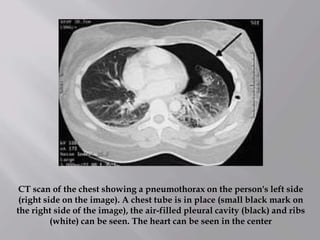

CT scan of the chest showing a pneumothorax on the person's left side

(right side on the image). A chest tube is in place (small black mark on

the right side of the image), the air-filled pleural cavity (black) and ribs

(white) can be seen. The heart can be seen in the center